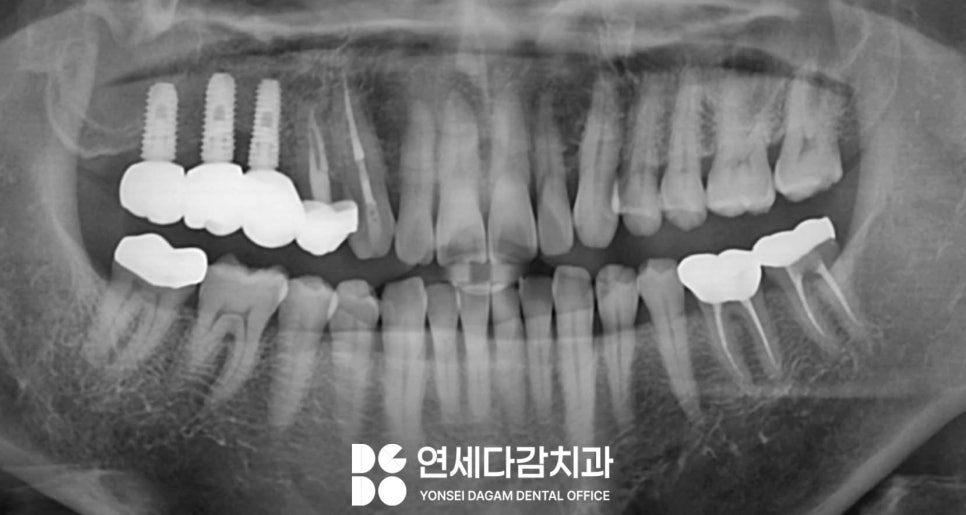

Caldwell-Luc Operation을

받은 환자들의 경우,

상악동 골벽에 결손이 발생한다는

전형적인 특징이 있습니다.

의도적으로 만든 공간이

다 닫히지 않고 일부 골결손 상태로

남아있는 경우가 많기 때문입니다.

이러한 골벽이 상실된 채로

오래 지내다 보면

임플란트 식립에 필요한 뼈가 부족하여

치료가 까다로워질 수밖에 없습니다.

임플란트 치료에서 중요한 것은

초기 고정력을 확보하는 것입니다.

따라서 이러 경우 CT 분석을 통해

사용할 수 있는 뼈를 미리 정확히 확인하고,

필요한 경우 추가적인 골이식술을

동반하여 진행해야 됩니다.

송파구 치과 에서는 이렇게 다양한 각도로

3차원적으로 구조를 살펴보며

염증의 범위를 살펴봅니다.

또한 결손 부위를 피해 가능한

건강한 골조직에 위치하도록

신중하게 각도와 깊이를 계획하고,

적절한 크기와 길이의

인공 치근(Fixture)을 선택하였습니다.

이후 염증 조절과 정기 검진을 통해

관리를 철저하게 하여

최종 보철물 세팅을 안정적으로

마무리할 수 있었습니다.

송파구 치과 에서 치료 전에 있었던

심한 악취와 고름 문제를

개선할 수 있었습니다.

현재도 꾸준히 정기 검진과

예방적 관리를 받으며 철저한 사후 관리를

지속하고 있으며,

최근 정기 검진 결과

임플란트가 문제없이

잘 유지되고 있는 것을 확인했습니다.